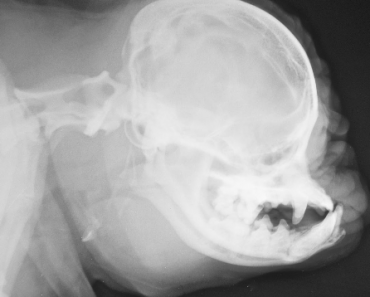

In a new study published today in the journal PLOS ONE, scientists from the University of Surrey, working with an experienced breeder in the Netherlands, examined how the skull and brain of toy dogs change when a Brussels Griffon with is crossed with an Australian Terrier. The succeeding hybrid puppy is then back crossed to a Brussels Griffon to give some of the features of the Brussels Griffon, but keeping the longer skull of the Australian Terrier.

The results from the study showed it is possible to breed a dog which had the external features of a short-nosed Brussels Griffon and reduce the risk of Chiari malformation, a debilitating condition found in toy dogs and affecting 1 in 1,280 humans. The disease is characterised by premature fusion of skull bones forcing parts of the brain to push through the opening in the back of the skull causing fluid filled cavities to develop in the spinal cord. Chiari malformation causes headaches, problems with walking or even paralysis and has become prevalent in some toy breed dogs as a result of selective breeding.

The breeder, Henny van der Berg, proposed the project idea after an accidental mating between two of her dogs. The four-year study analysed five traits on magnetic resonance images (MRI) scans and how they changed generation by generation in the family of 29 dogs. Using a careful selection of head shape and MRI scans over two generations, the findings revealed it was possible to breed a dog which had the external features of a Brussels Griffon, but is less susceptible to Chiari malformation.